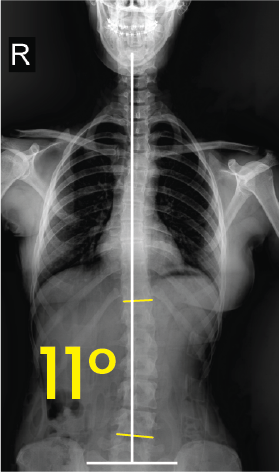

Torakal omurgada sağa doğru 18 derece eğriliği gösteren röntgen görüntüsü.Toraks röntgeninde orta çizgiye göre 11 derece eğimli omurga görünümü.